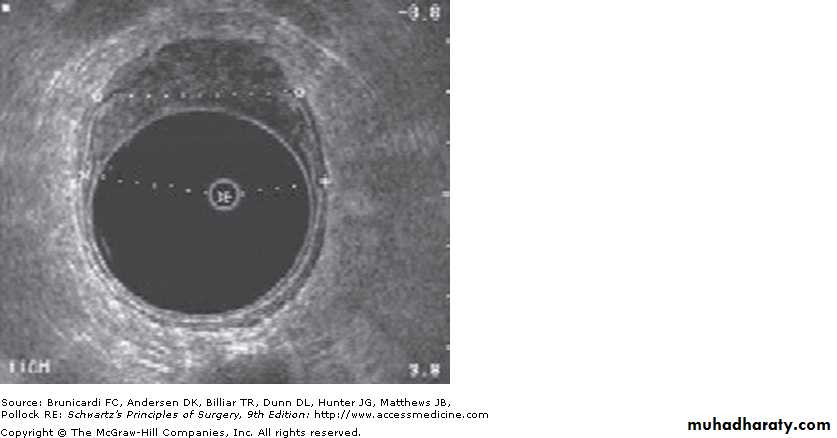

- endoscopic ultrasound

6- endoscopic ultrasound helpful in staging of tumor